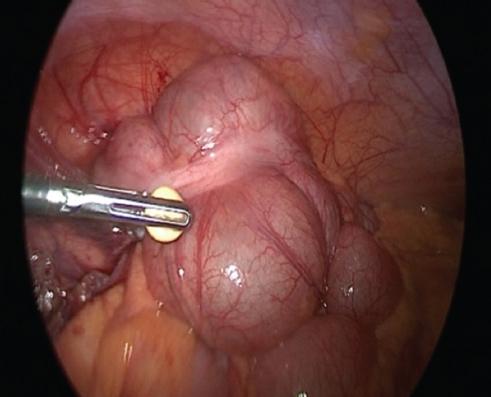

Cirugía realizada: apendicectomía laparoscópica. Abordaje con técnica de Hasson a través de una incisión umbilical de 1 cm, posteriormente se coloca un trocar umbilical de 12 mm y se inicia capnoperitoneo hasta 12 mmHg. Se introduce una lente de 30° y se realiza laparoscopia diagnostica. Se procede a la colocación de trocares de 5 mm, de región suprapúbica y de flanco izquierdo.

Hallazgos: adherencias laxas del epiplón a la pared. Líquido libre purulento de aproximadamente 20 ml. Apéndice vermiforme de 10 cm, hiperémico, edematoso en toda su extensión, con placas fibrinopurulentas. Se realiza apendicectomía y se maneja el muñón con técnica de Halsted. Sin complicaciones, con sangrado mínimo (Figs. 2 and 3).